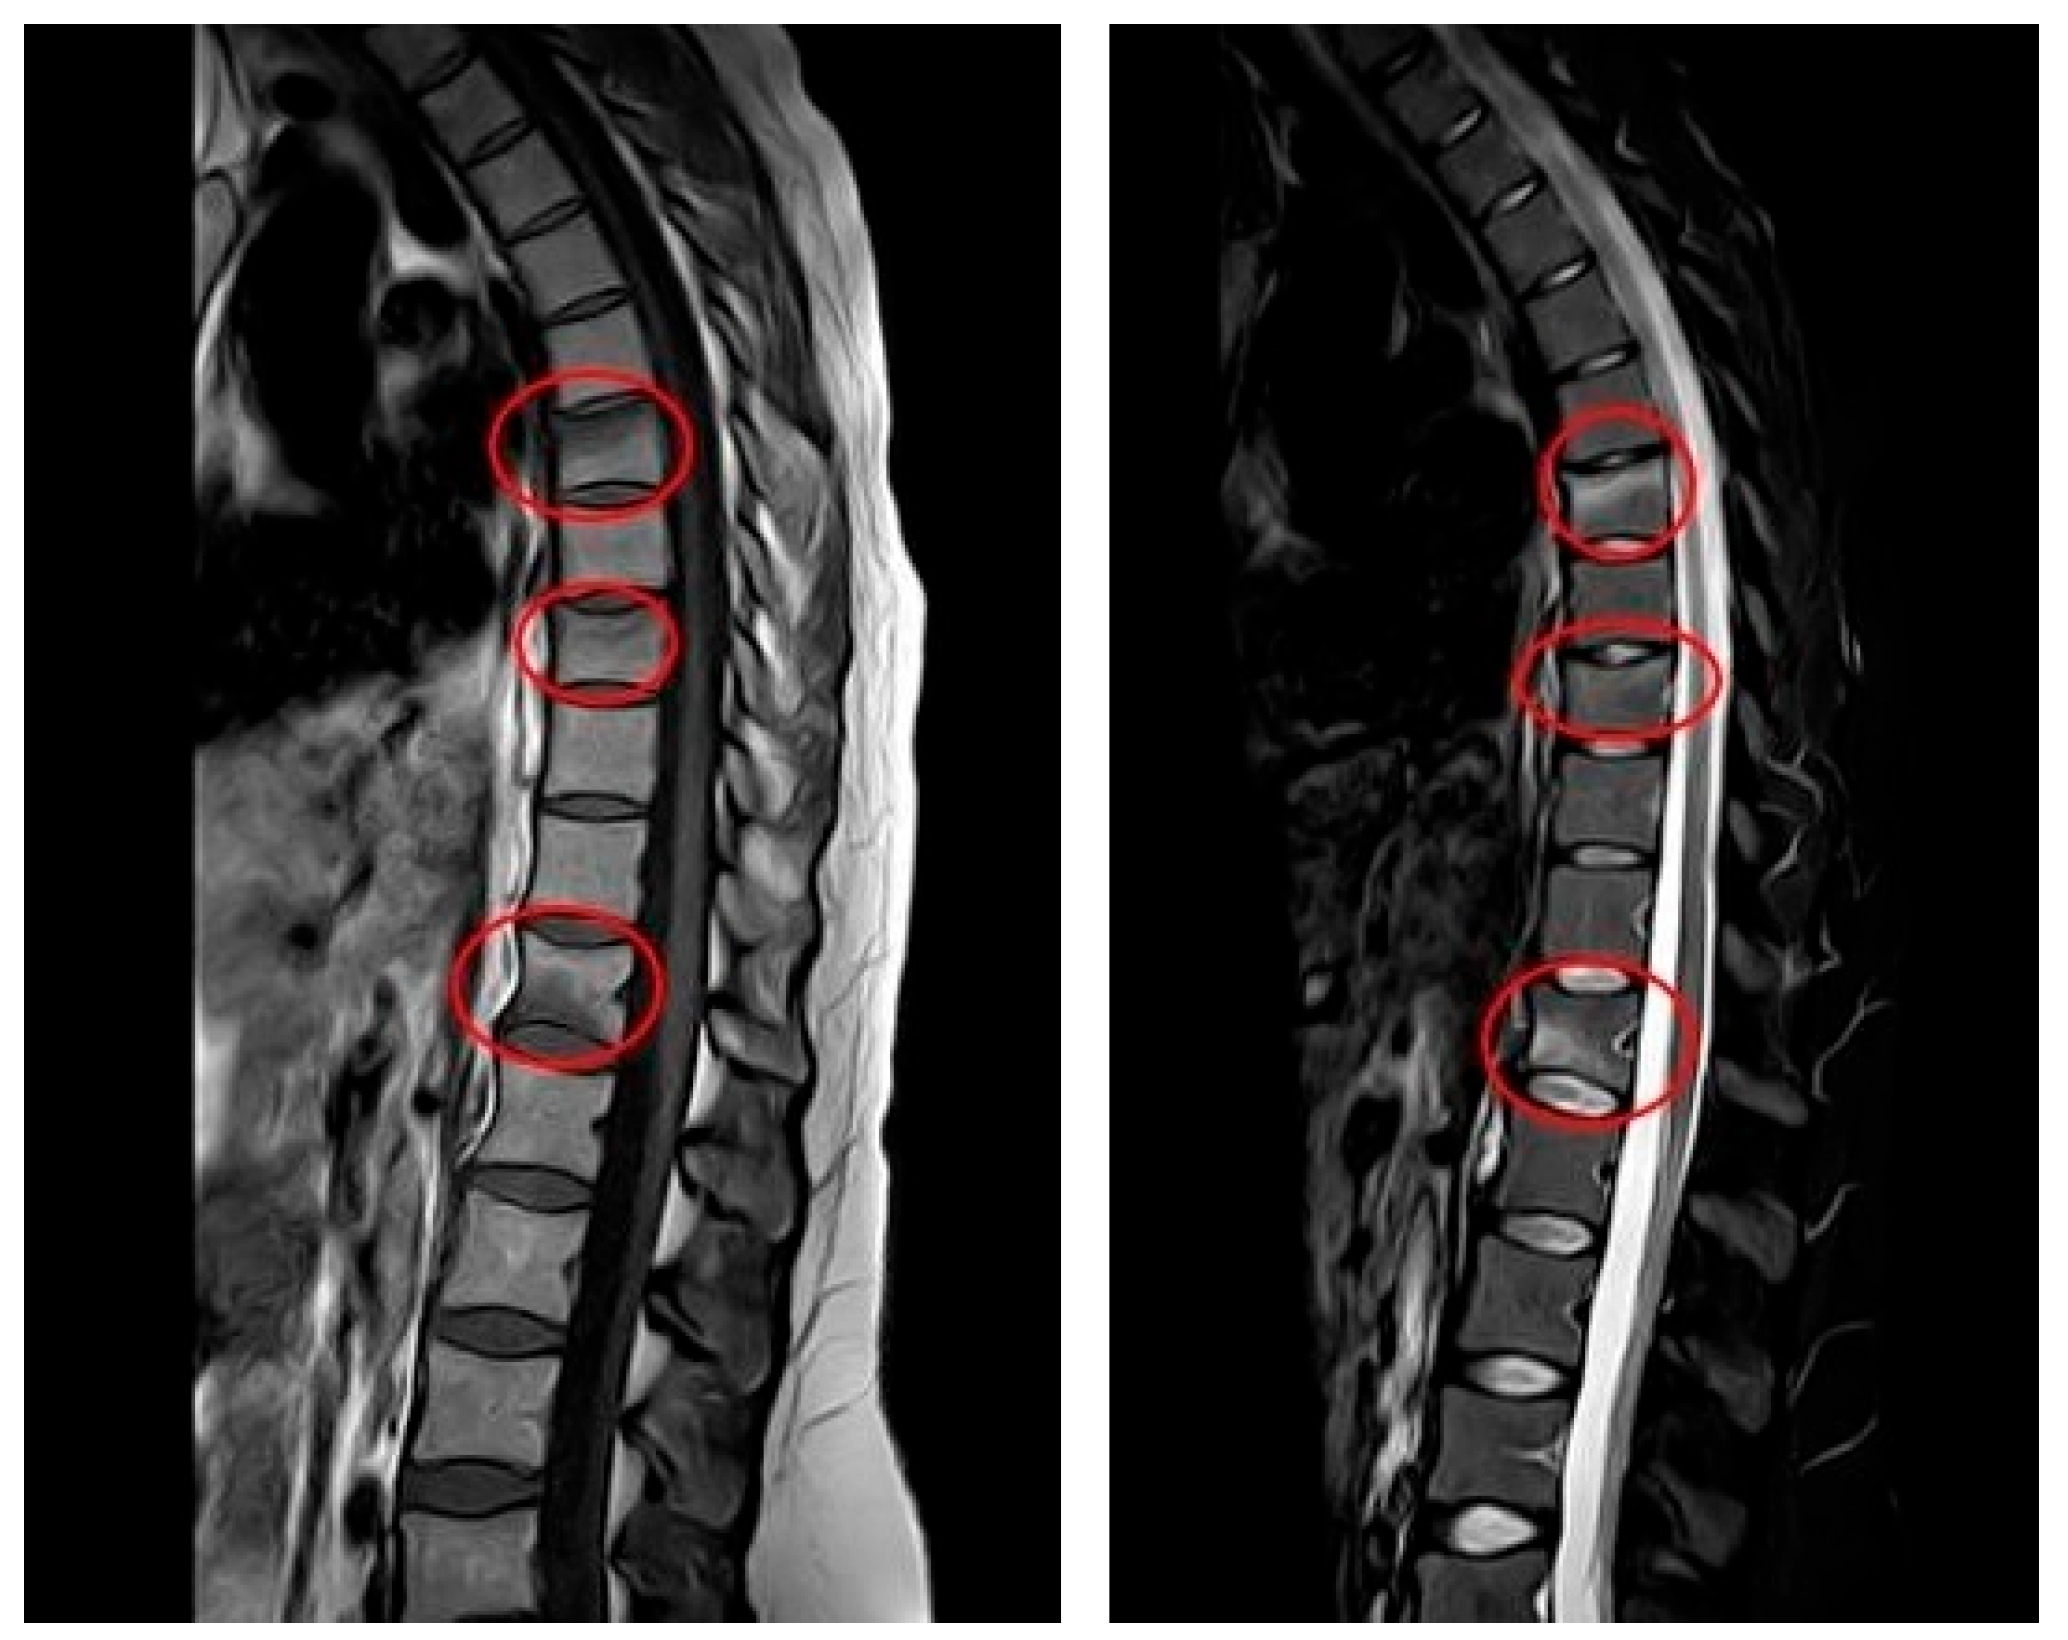

The patient delivered without complications in December 2023. The lower back pain persisted even after delivery. In January 2024, the gynecologist conducted a postpartum follow-up examination due to the patient’s presentation of multiple symptoms, including severe pain. Subsequently, magnetic resonance imaging (MRI) was ordered for further evaluation. The results indicated very slight deformities in the T7, T9, and T12 vertebral bodies due to vertebral fractures located in the disco-somatic regions. There was also a linear edematous band present in the vertebral bodies, along with some depression in the superior limits of T7 and T9, and a slight depression in the inferior limit of T12. No additional pathologies, such as herniations or disc issues, were observed in this MRI (Figure 1). Consequently, the gynecologist referred the patient to the aforementioned Rehabilitation Department. It is important to note that, based on the presence of fractures, the gynecologist recommended avoiding breastfeeding to prevent further worsening of the condition; however, the patient refused to do so. Due to persistent and intensifying pain, the patient was referred to a physiatrist.

In January 2024, the patient presented to the clinic with her history and showing MRI results (Figure 1). Due to suspected PLO, Dual-energy X-ray Absorptiometry (DXA) was recommended. The results indicated a lumbar T-score of −3.4, which is indicative of osteoporosis (as values below −2.5 are considered below normal), and a femoral T-score of −1.3. Additionally, laboratory tests revealed low levels of calcium and vitamin D. Laboratory Workup for Osteoporosis consisted of the following steps:

Figure 1. MRI at initial diagnosis (January 2024, one month postpartum): MRI (T1—weighted sequence on the (left), T2—weighted sequence on the (right)) showing anterior wedge compression fractures at T7, T9 and T12, with linear bone marrow edema and mild depression of vertebral endplates. No disc herniation or spinal canal narrowing is present.